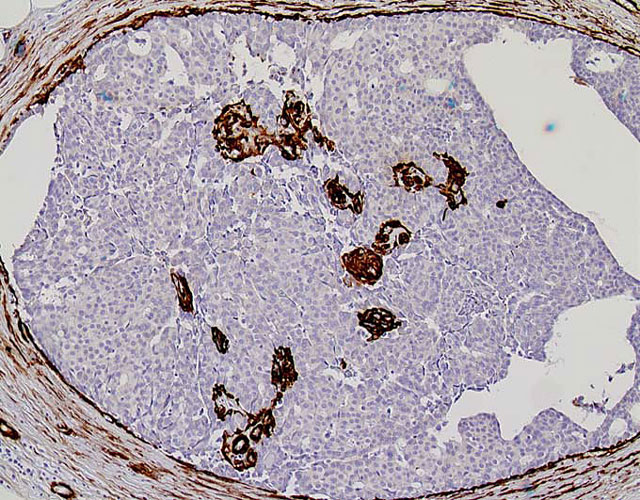

病変部拡大像(α−SMA抗体での免疫染色)